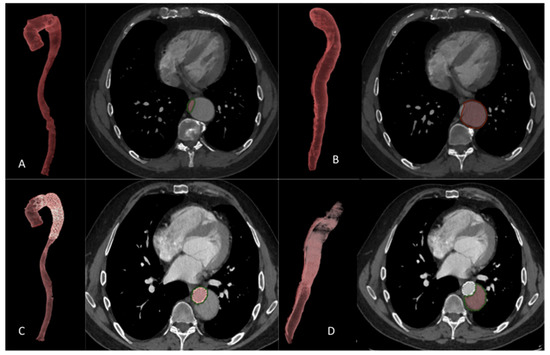

2.8. Volume Analysis

2.9. FL Status